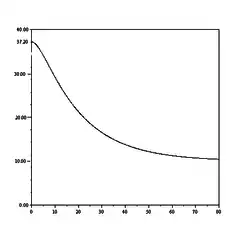

Une deuxième approche consiste à utiliser les lois de la conduction thermique et de supposer que le flux thermique est proportionnel à la différence de température entre le corps et l'air ambiant. Cette approche permet alors de modéliser la baisse de température par une fonction exponentielle :

Cependant cette modélisation n'apparait pas satisfaisante confrontée à la réalité de l'expérience. En effet, on note, sans pouvoir l'expliquer, que la baisse de température s'effectue en trois phases :

Le docteur Claus Henssge, professeur de médecine légale à l'université de Essen (Allemagne) a cherché à modéliser la décroissance thermique sous la forme d'une fonction de sommes d'exponentielle variable selon la masse de l'individu. Il propose alors la modélisation suivante :

où k est un paramètre dépendant de la masse M (en kg) de l'individu :

L'observation de ces deux fonctions permet de remarquer que

- la dérivée au temps t = 0 de la température est nulle, ce qui permet bien de modéliser le palier initial.

- La décroissance est d'autant plus lente que la masse de l'individu est élevée.